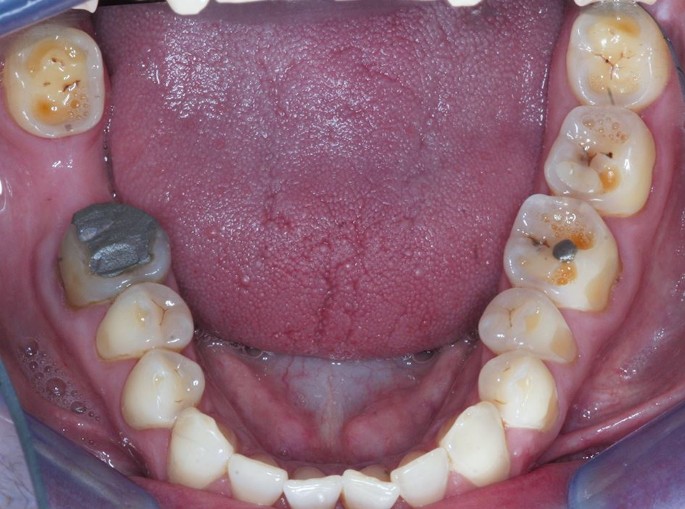

Signs of intrinsic acid-related dental erosion are commonly wear on the palatal aspects of maxillary teeth and the occlusal surfaces of mandibular molars, flattened occlusal contours and cupping of cusp tips. Maxillary buccal cervical erosion may also be present if the patient holds gastric contents in their cheeks. Restorations may stand proud and incisal edges may become grooved. As enamel is eroded away, there may be a blueish tinge, and then teeth may appear darker and yellow dentine starts to shine through, often leaving a peripheral ring of enamel.2 Erosive tooth wear tends to leave smoother surfaces compared to other types of wear, although they often occur in combination and a good history will aid diagnosis (Fig. 1, Fig. 2 and Fig. 3 demonstrate these signs, and as such rapid wear had occurred, there has not been any dento-alveolar compensation).

These clinical findings, particularly in the absence of significant dietary acids or a disclosed history of an eating disorder, present an opportunity for dentists to ask more questions about a history of GORD. Patients may not be aware of the symptoms of GORD. Dentists are therefore in a unique role as they may be the first healthcare professional to diagnose possible signs of GORD and question the patient.